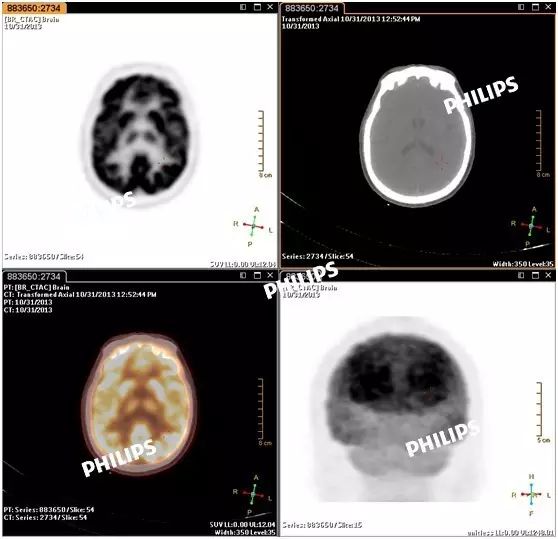

点击屏幕左上方的轴向调整按键。图像即可显示为调整后的图像: